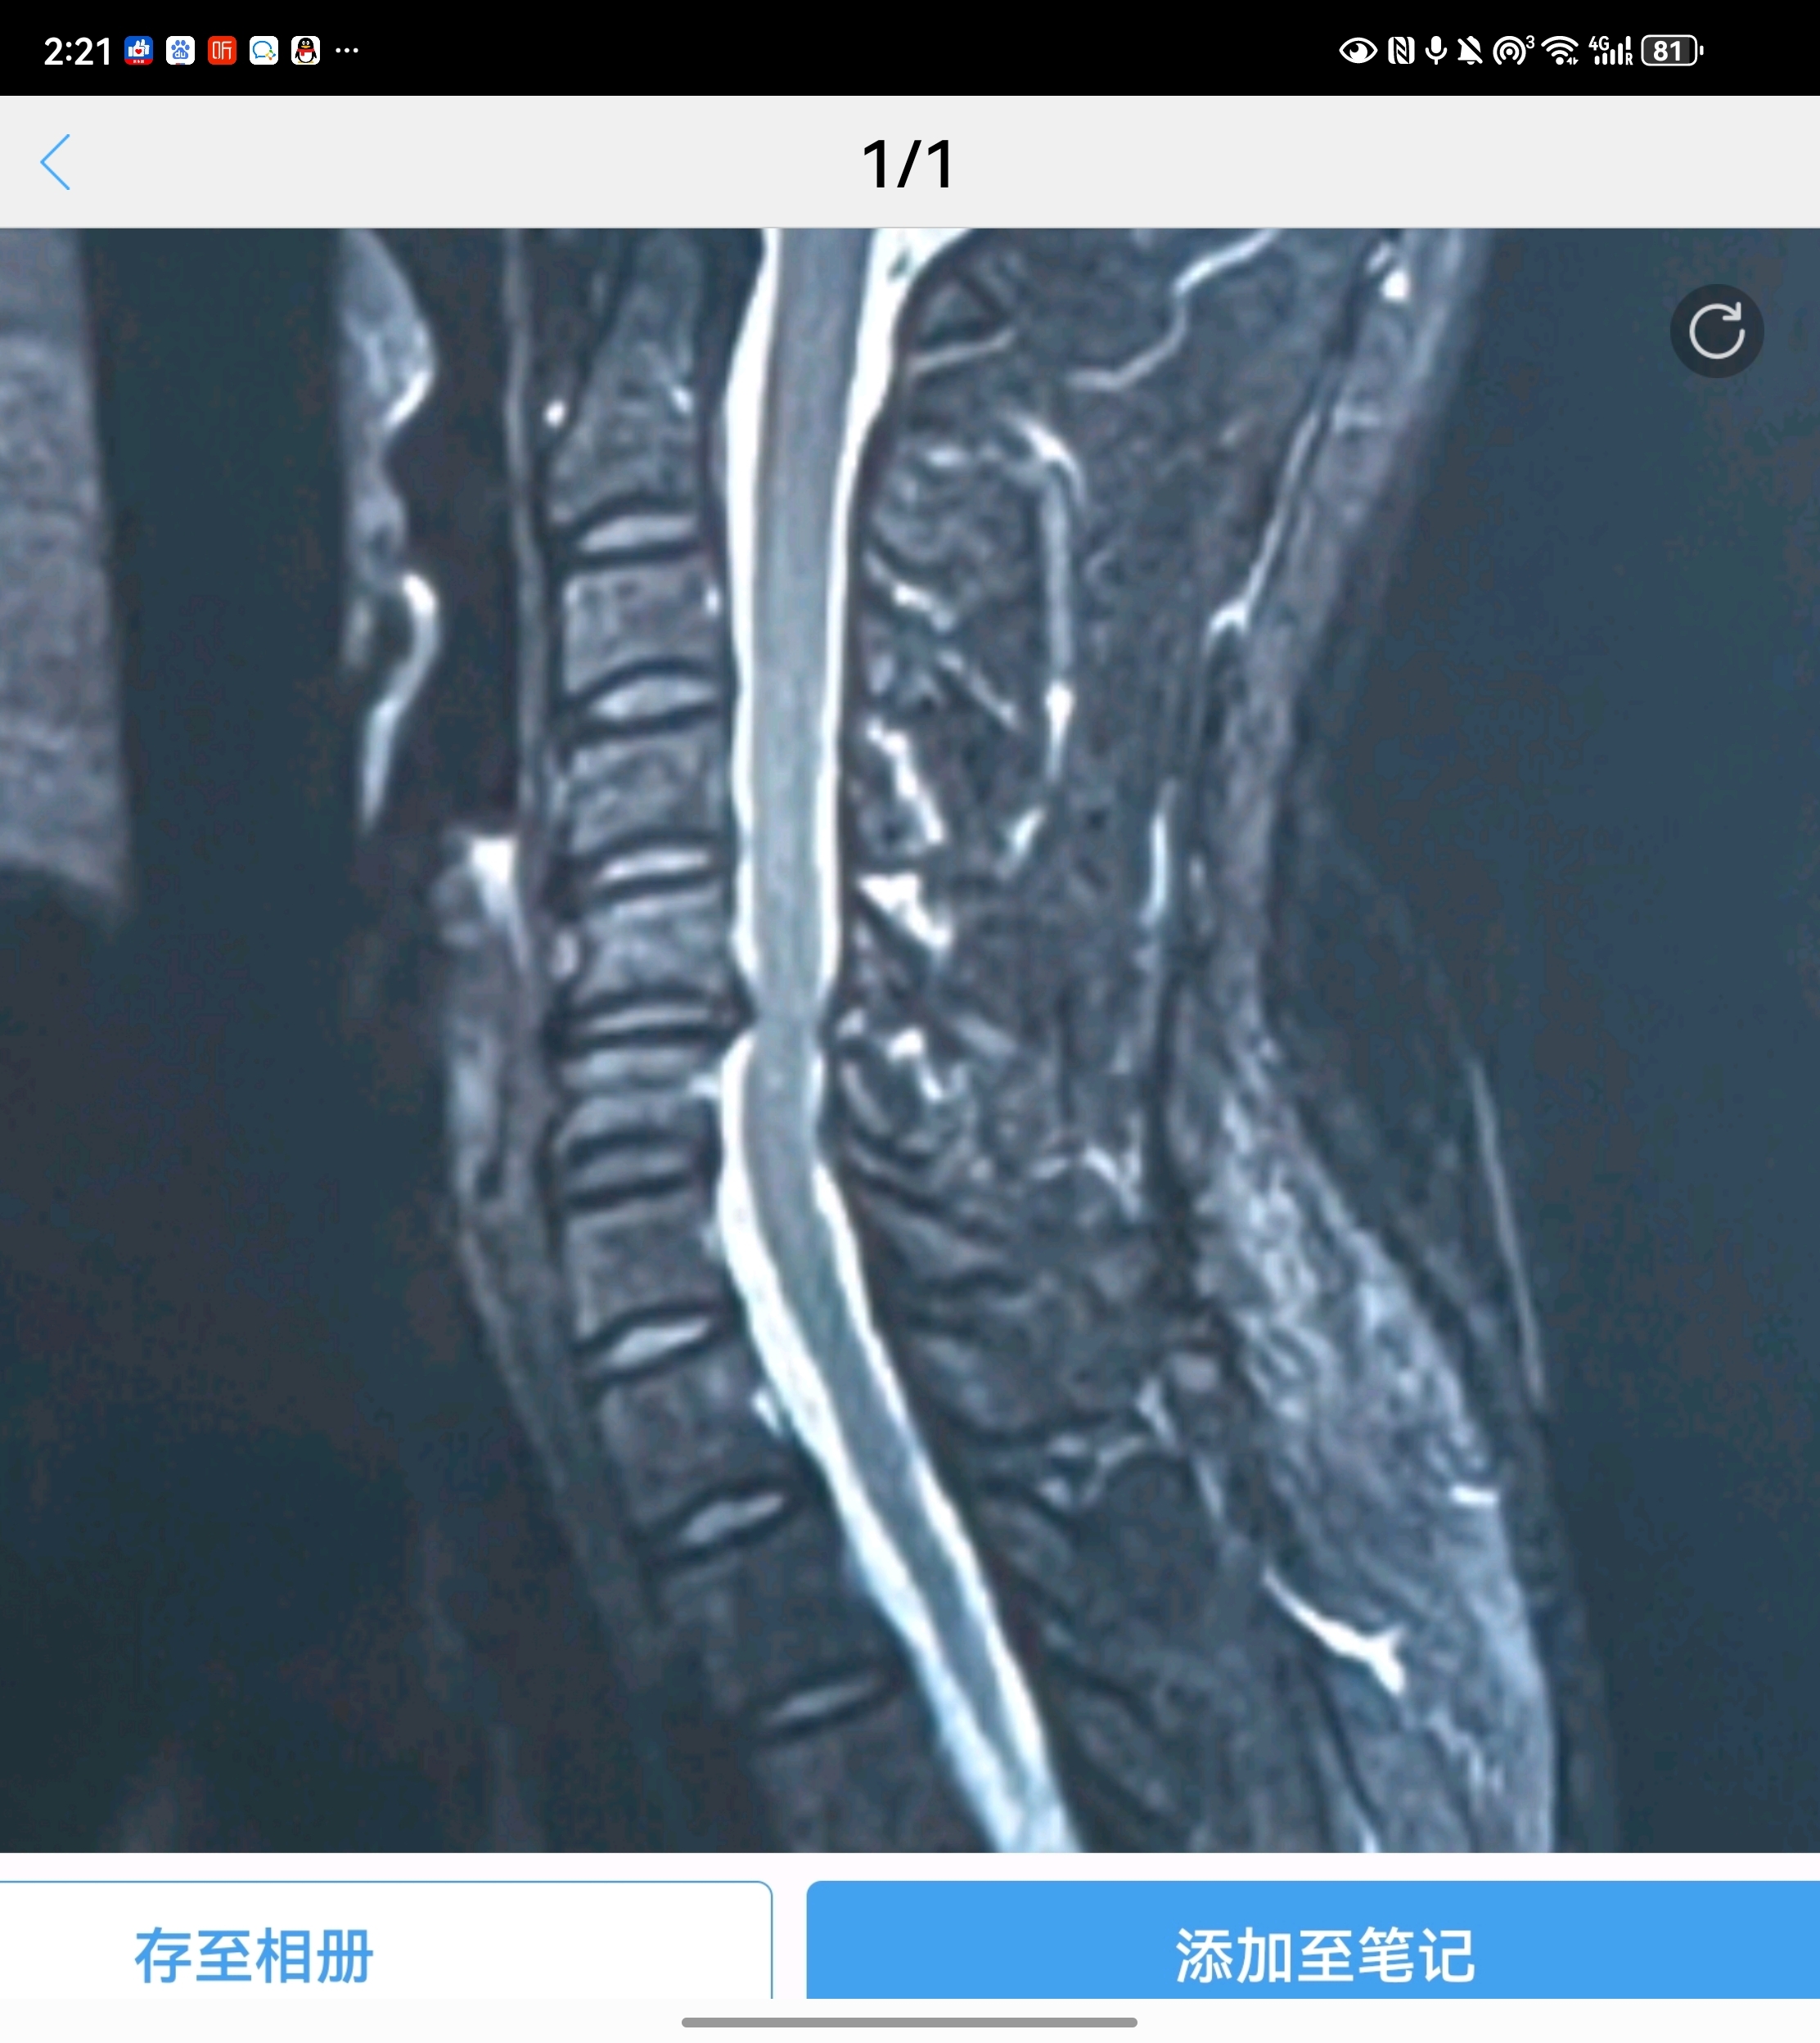

許多患者在檢查頸椎的時候,發(fā)現(xiàn)自己的報告單上寫著“頸椎間盤突出、脊髓變性”等字樣,這個時候醫(yī)生就會告知情況嚴重,需要手術!這就讓不少患者非常糾結(jié),真的就必須手術嗎?而在網(wǎng)上一查,都說脊髓變性了肯定要手術,而且術后可能還恢復不好。這是真的嗎?最近,宣武醫(yī)院王作偉主任就接診了一位62歲的女性患者。她在1年前就出現(xiàn)了右側(cè)上肢疼痛,雙下肢的酸麻、行走不穩(wěn)的情況,去了當?shù)蒯t(yī)院檢查后發(fā)現(xiàn)是脊髓型頸椎病,并告知脊髓變性了,需要盡快手術。當時她覺得自己的癥狀不是特別嚴重,就沒有立即手術,服用了一些藥物,做了保守治療。但是今年她的癥狀越來越重,行走困難,要人扶著才能走,上肢也疼痛劇烈,什么活兒也干不了。這次,家里人就很重視了,去了不少醫(yī)院,都建議她盡快手術,有的醫(yī)生還說脊髓變性了,脊髓有了一定損傷,術后可能就恢復不好了。這讓她們一家很擔心,現(xiàn)在已經(jīng)不是手術不手術的問題,而是做了手術能不能恢復的問題了。為了進一步治療,他們決定去北京大醫(yī)院再看看,最后找到了王主任。脊髓型頸椎病出現(xiàn)的脊髓變性是怎么回事?脊髓型頸椎病是頸椎病眾多類型中最危險的一型,它之所以這么危險,就是因為壓迫到脊髓。那報告當中的脊髓變性又是怎么回事?簡單來說,就是脊髓受壓久了,脊髓缺血了,這種情況持續(xù)時間長了就產(chǎn)生了脊髓變性。如果再不盡快處理,繼續(xù)發(fā)展下去就會有脊髓壞死的可能,到那個時候患者就會癱瘓。所以,一旦確診為脊髓型頸椎病后,都是建議盡快手術,避免病情向最嚴重的情況(癱瘓)繼續(xù)發(fā)展。脊髓變性在頸椎的核磁共振片子上顯示很明確,椎管內(nèi)正常的脊髓是暗黑色的一條,而脊髓變性的地方顏色呈現(xiàn)變白、變淺。就像這位患者的片子,在頸5-6、頸6-7處的椎間盤有突出,而且嚴重壓迫到了后面的脊髓,尤其是頸5-6水平處的脊髓顯示變淺,提示有脊髓變性。術前影像學資料:脊髓變性了再做手術后還能完全恢復嗎?這還是需要根據(jù)患者術前的具體情況而定,如果患者術前脊髓變性很輕、時間短,術后的各項功能還是可以恢復的;但如果患者術前脊髓受壓時間特別久,變性也很嚴重,術后的癥狀就會恢復得很慢,甚至一部分功能出現(xiàn)不可逆的損傷,這時就不能完全恢復了。但相比完全癱瘓來說,盡早手術給脊髓減壓還是非常有必要的。這位患者在了解后就馬上同意了手術,王主任根據(jù)她的具體情況為她定制了微創(chuàng)的頸前路手術,并在其后為她成功完成手術。手術中在保護周圍神經(jīng)、脊髓、血管等組織的情況下,將兩個節(jié)段的椎間盤突出切除,給脊髓進行了徹底減壓,并進行內(nèi)固定建立頸椎的穩(wěn)定性。術后,她右上肢疼痛癥狀得到很快緩解,下肢麻木也得到了一定改善,在術后三天,她已經(jīng)可以自己獨立行走了,效果很好。術后影像學資料:其實,脊髓型頸椎病只要確診了,都是需要手術的,而且早做手術要比晚做的效果好很多,有時甚至是天壤之別,所以還是建議大家能早做就早做,不要拖到后面脊髓變性得很嚴重了再做。